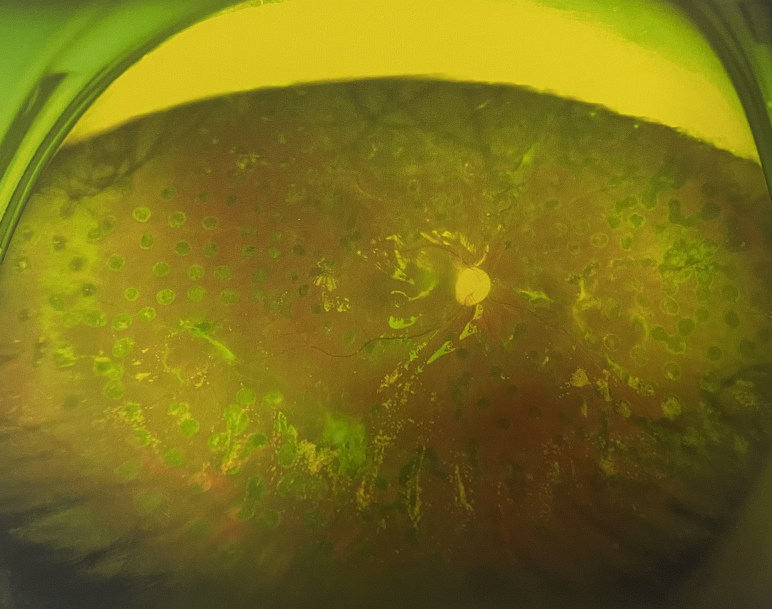

右眼術(shù)前

右眼術(shù)后